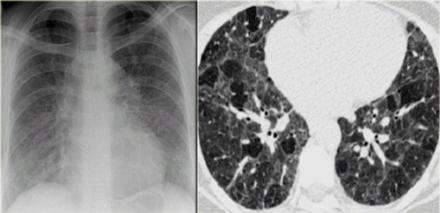

肺纤维化胸片图解

肺纤维化胸片图解,肺纤维化图片解剖图

胸片显示双侧中央支气管扩张伴有分支管状实变.

同时,小叶距离网状增厚,表明已有弗成逆的纤维化.